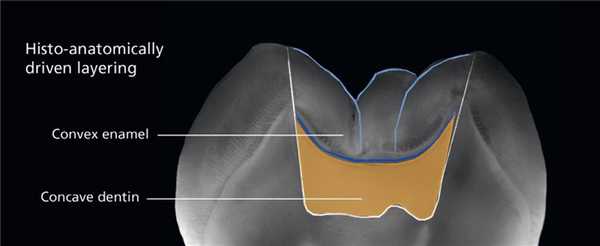

Цель данной методики состоит в максимальной имитации собственных тканей зуба. Сначала выполняют build-up, имитирующий структуру коронки: на окклюзионной поверхности дентин имеет вогнутую форму, а эмаль - выпуклую. Данную биологическую особенность нужно учитывать (Bazos et al., 2011) при внесении порций композита (фото 1). На отпрепарированной окклюзионной поверхности достаточно просто идентифицировать структуру дентина и эмали, таким образом определяя до какого уровня необходимо адаптировать соответствующие виды материалов. Кроме того, такой подход позволяет минимизировать риск развития эффекта «непопадания» в цвет, который часто визуализируется после окклюзионной коррекции пломбы.

Фото 1. Естественный вогнутый контур дентина и выпуклый контур эмали.